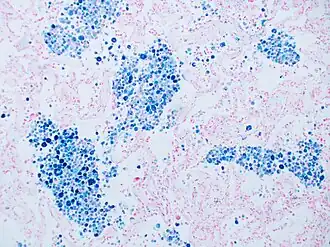

Stain for iron

Prussian blue is a common histopathology stain used by pathologists to detect the presence of iron in biopsy specimens, such as in bone marrow samples. The original stain formula, known historically (1867) as "Perls Prussian blue" after its inventor, German pathologist Max Perls (1843–1881), used separate solutions of potassium ferrocyanide and acid to stain tissue (these are now used combined, just before staining). Iron deposits in tissue then form the purple Prussian blue dye in place, and are visualized as blue or purple deposits.[54]

Prussian blue staining, highlighting the hemosiderin pigment as blue. -

Prussian blue stain